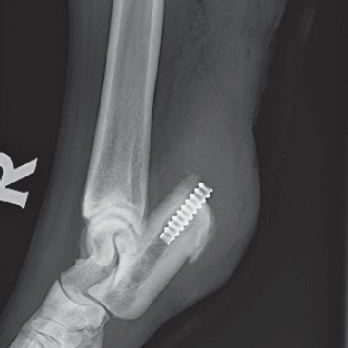

Gastrocnemius Tendon Reconstruction Under Construction. Share this post Share on FacebookShare on Facebook TweetShare on Twitter Pin itShare on Pinterest Share on LinkedInShare on LinkedIn Share on WhatsAppShare on WhatsApp Project navigationPreviousPrevious project:Tarsus Medial Collateral LigamentNextNext project:Elbow